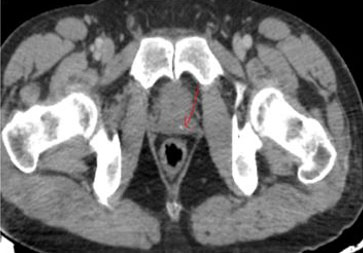

Otherwise, the patient claims primary infertility of 20 years since marriage, he underwent a spermiogram that revealed oligoasthenospermia. Pelvic computed tomography (CT) scans showed calcifications in the prostate (Figure 3) and seminal vesicles (Figure 4), pelvis magnetic resonance imaging (MRI) scan confirmed the CT scan findings.

Figure 4: Pelvic HRCT: microliths in the seminal vesicles.